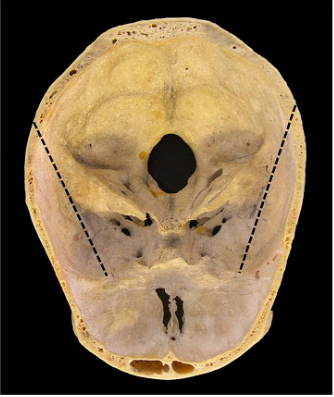

Methodology: We took the head of a specimen, emptied the cranial cavity and determined a point of reference, situated approximately 2cm behind the external acoustic meatus. Then we traced a line from this point up to the midpoint of the margin that separates the anterior cranial fossa from the middle cranial fossa, bilaterally. Based on these reference lines, we cut the head.

After this, for both sides, we traced a line from this point up to the midpoint of the margin that separates the anterior cranial fossa from the middle cranial fossa; this margin being formed by the smaller wing of the sphenoid bone and by the horizontal lamina of the frontal bone (Figure 2). Based on these reference lines, we made the cuts of the part, which resulted in three segments: A central segment with a triangular shape and two lateral segments (Figure 3).